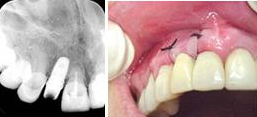

Figura n°1. Caso clínico: Paciente de 46 anos de idade, já portadora de 4 implantes, colocados há 6 anos, compareceu ao consultório após a perda da coroa do dente 12 com fratura da raiz.

Figura n°2. A análise radiográfica, mostrou uma raiz com muito pouca implantação, reação apical e ao exame clínico uma provável linha de fratura, transversal, alterando o ligamento periodontal no terço médio da raiz. Assim a raiz foi condenada, e indicado à paciente um implante imediato. Na radiografia pode-se observar outras alterações nos ápices dos dentes 13 e 14.

Figura n°3. Esta é a fotografia antes da cirurgia para implante. A imagem não ficou boa, mas pode-se notar com atenção uma linha de fratura iniciando na região vestibular com direção à distal.